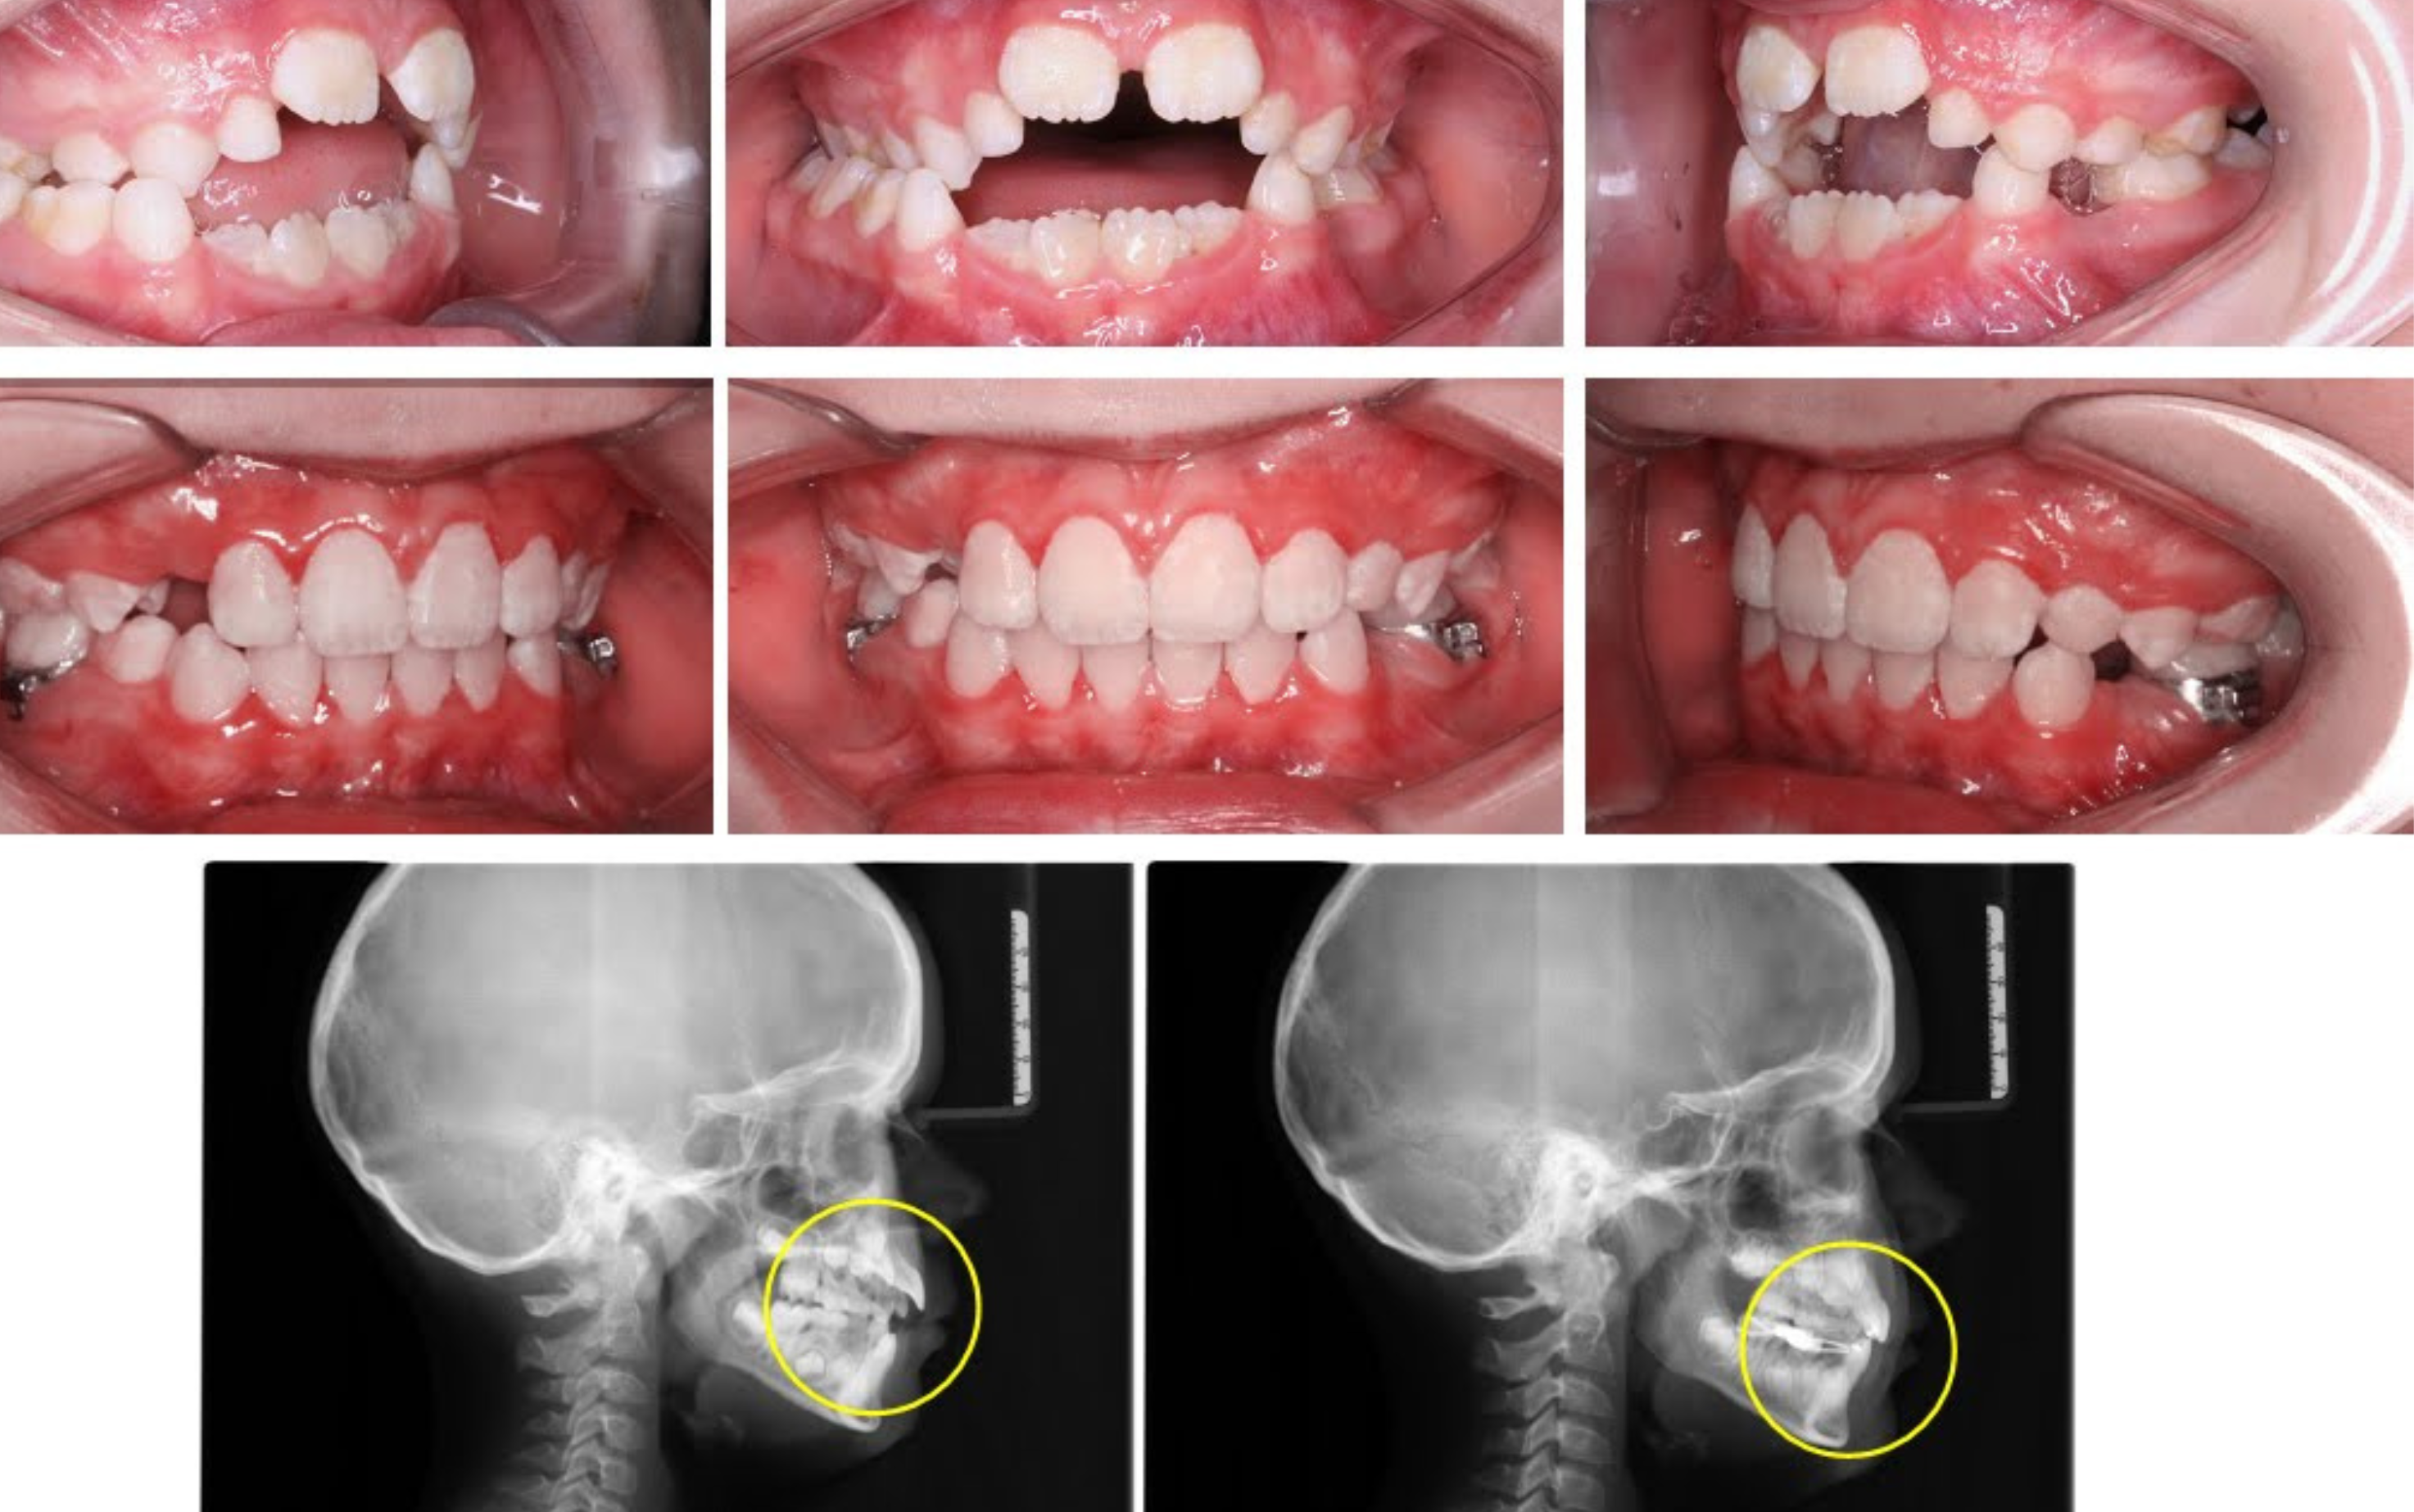

An orthopantomogram (OPG), also known as a panoramic dental X-ray, is a comprehensive two-dimensional image of the entire mouth. It captures the teeth, jaws, temporomandibular joints (TMJs).

Many Kid's suffer from deleterious oral habit of Thumb sucking Mouth Breathing which can have a very bad effect on erupting dentition of your kids .